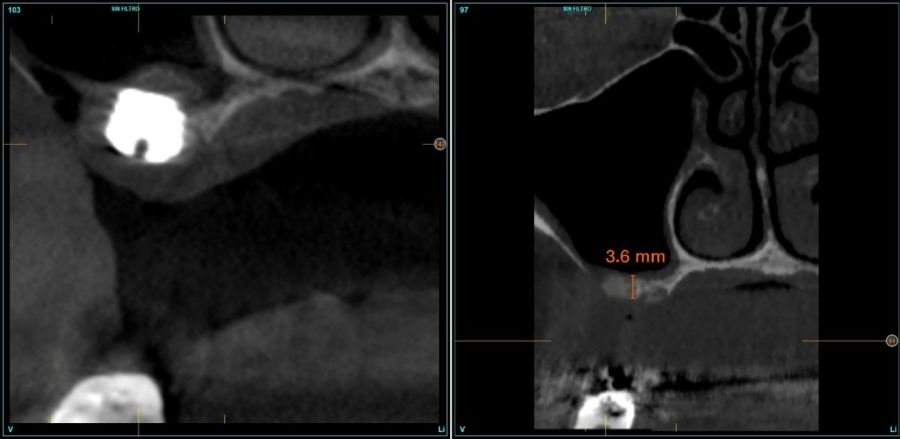

Fueron reclutados de forma retrospectiva pacientes en los que se llevase a cabo una inserción de implantes dentales de 4,5 mm de longitud en crestas óseas residuales de hasta 4,5 mm de altura con elevación de seno transcrestal, utilizando como material de injerto hueso autólogo obtenido del fresado y PRGF-Endoret, unido a la inserción directa con anclaje en la cortical desde junio de 2020 hasta septiembre de 2021. Antes de la colocación de los implantes, todos los pacientes fueron evaluados mediante modelos diagnósticos, exploración intraoral y un CBCT (Cone Beam Computed Tomography), cuyo análisis se realizó con un software especializado (BTI-Scan III), para conocer la altura exacta de la cresta ósea residual y la densidad, y poder adaptar en consecuencia el protocolo y el implante a colocar. Como protocolo preoperatorio, se administró una premedicación antibiótica con amoxicilina (2 g por vía oral) una hora antes del procedimiento, junto con paracetamol (1 g por vía oral) como analgésico. Tras la intervención, los pacientes continuaron con un tratamiento antibiótico de amoxicilina (500-750 mg por vía oral cada 8 horas, según el peso) durante cinco días. La colocación de los implantes fue realizada por un mismo cirujano utilizando la técnica de fresado biológico, caracterizada por bajas revoluciones y ausencia de irrigación, ajustando el procedimiento a la densidad y volumen del lecho óseo receptor para asegurar una adecuada estabilidad primaria del implante8-9.

Fueron reclutados 16 pacientes en los que se colocaron 18 implantes que cumplieron los criterios de selección anteriormente descritos. La media de edad de los pacientes fue de 58,76 años (+/- 11,43) y 12 de los pacientes fueron mujeres. La media de la altura ósea previa de las localizaciones de los implantes fue de 3,96 mm (+/- 0,38) con un rango comprendido entre 3,18 mm y 4,43 mm.

En todos los casos se realizaron elevaciones óseas desde los 0,2 hasta los 1,3 mm. En la Figura 2 se observa la altura ósea inicial y final para cada uno de los implantes. Las posiciones más frecuentes de los implantes incluidos en el estudio fueron en 16 y en 26 con 33,3% respectivamente, y la menos frecuente en posición 27 (11,1%). Todas las posiciones se muestran en la Figura 3.